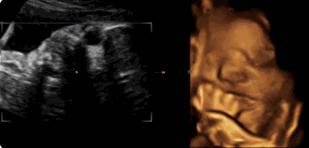

麻麻,我正在挠耳朵